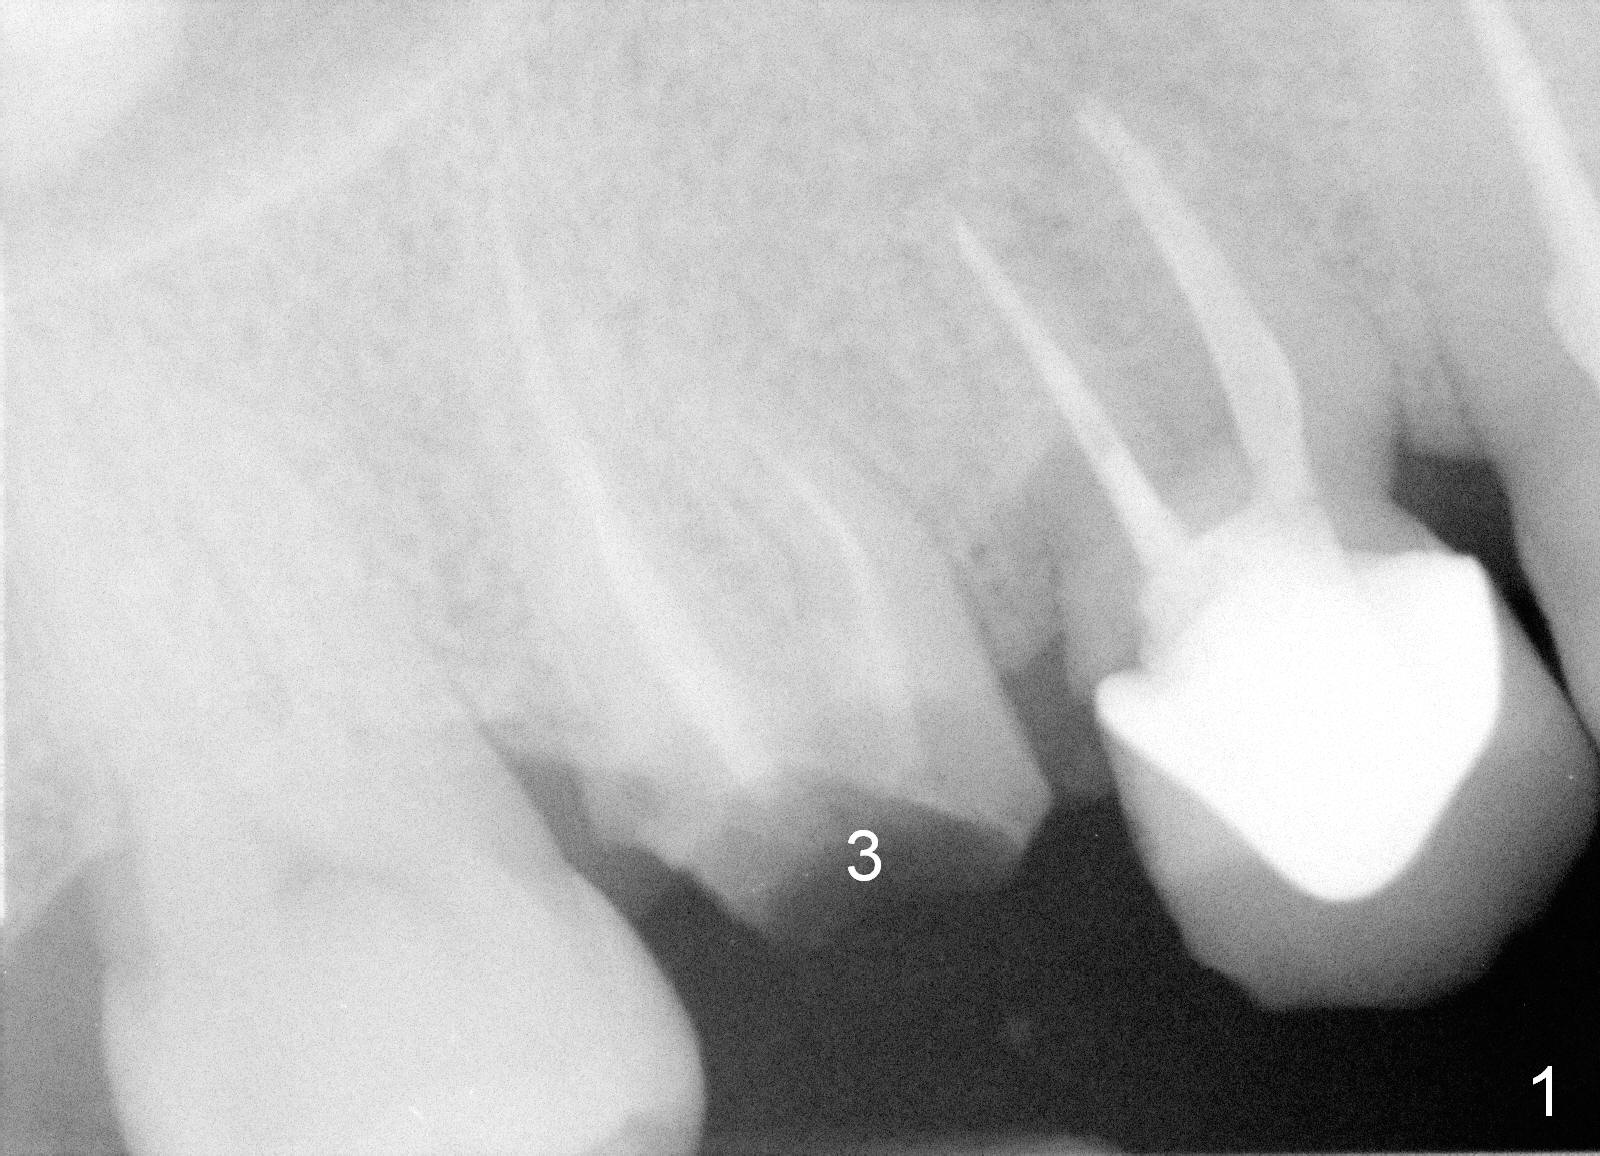

A 47-year-old man has multiple restoration. The crown of the tooth #3 has been recemented several times in the last 3 years (Fig.1). Before placement of an immediate implant at #3 (Fig.2), the root of the adjacent tooth is diagnosed to have crack and replaced by an immediate implant (Fig.3).